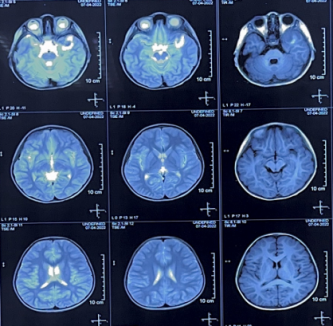

PET-CT(2022.5.12):

左侧眼眶后壁及左侧颞骨骨质破坏,伴颞面及左侧颞叶高密度影,代谢活性弥漫增高,有少量肿瘤代谢活性残余,评估为部分缓解(PR)。

PET-CT(2023.05.12):

颅骨、颞面及左侧颞叶高密度影消失。

PET-CT(2023.09.15):左肾上腺区术后改变,术区未见肿瘤代谢活性病变,持续CR。